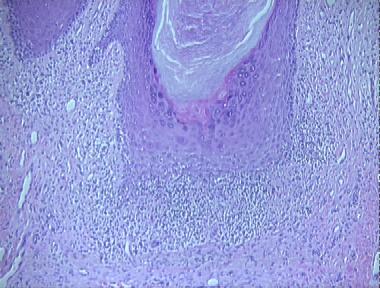

hypertrophic lichen planus

Histologic Features